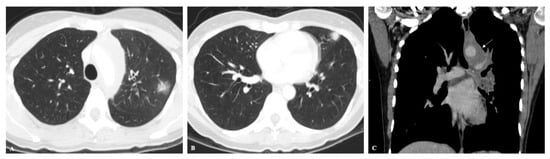

2.1. Lung Nodule or Mass

2.4. Disseminated Infection

| Lung Nodule or Mass | Non-Resolving Pneumonia | Chronic Cavitating Disease | Disseminated Infection | Bronchiectasis & Asthma | |||||

| Imaging Clue | Dx | Imaging Clue | Dx | Imaging Clue | Dx | Imaging Clue | Dx | Imaging Clue | Dx |

| Adenopathy | Coccidioidomycosis Histoplasmosis | Consolidation + large nodules/masses | Blastomycosis Cryptococcosis Paracoccidioidomycosis | Grape-skin cavities + Lymphadenopathy | Coccidioidomycosis | Miliary ARDS Extrathoracic | ++ Histoplasmosis Coccidioidomycosis | High-attenuation mucus plugging Finger in glove | ABPA |

| Lung Mass | Cryptococcosis Blastomycosis | Adenopathy | Coccidioidomycosis Histoplasmosis | Calcified nodes | Histoplasmosis | ||||

| Flip-flop node SUVmax > lung mass | Granulomatous Infection | ||||||||